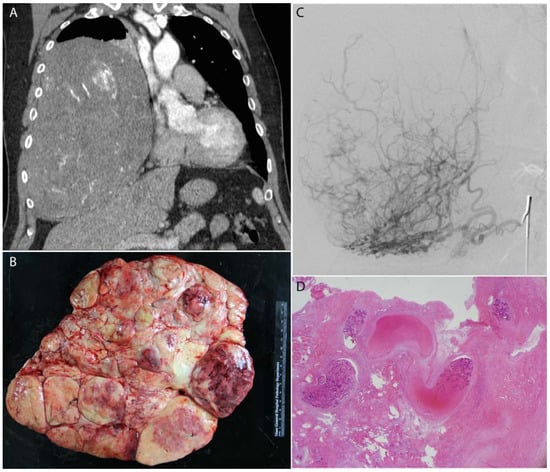

Figure 5.

A leiomyosarcoma metastasis to the liver was embolized with 100–300 μm, doxorubicin-eluting microspheres to reduce tumor size and vascularity prior to surgical resection. Selective catheterization (A) of the tumor was performed, with proper positioning confirmed by cone-beam CT (B). Post-procedure CT (C) demonstrates no residual vascularity within the lesion. Following liver resection, microspheres were identified within the blood vessels in the tumor bed without any evidence of viable metastatic tumor (D).

Figure 6.

A breast cancer metastasis to the liver was embolized with 100–300 μm, doxorubicin-eluting microspheres to reduce tumor size and vascularity prior to surgical resection. Selective catheterization (A) of the tumor was performed, with delivery of the microspheres within the blood vessels of the tumor (B). Post-procedure CT (D) demonstrates complete response of the tumor as indicated by fibrosis alone without any evidence of residual tumor compared to the pre-procedure CT (C).